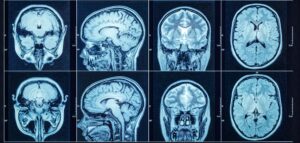

Being diagnosed with brain cancer can feel overwhelming, but treatment has come a long way. Depending on the type, size, location, and whether the tumor is benign or malignant, your care team will develop a personalized plan to provide the best chance for recovery and quality of life.

Brain Cancer Awareness is about more than a diagnosis—it’s about education, early detection, and support for those impacted. Although brain cancer is relatively rare, it can be life-altering. Raising awareness helps ensure symptoms aren’t ignored and encourages people to seek timely care.